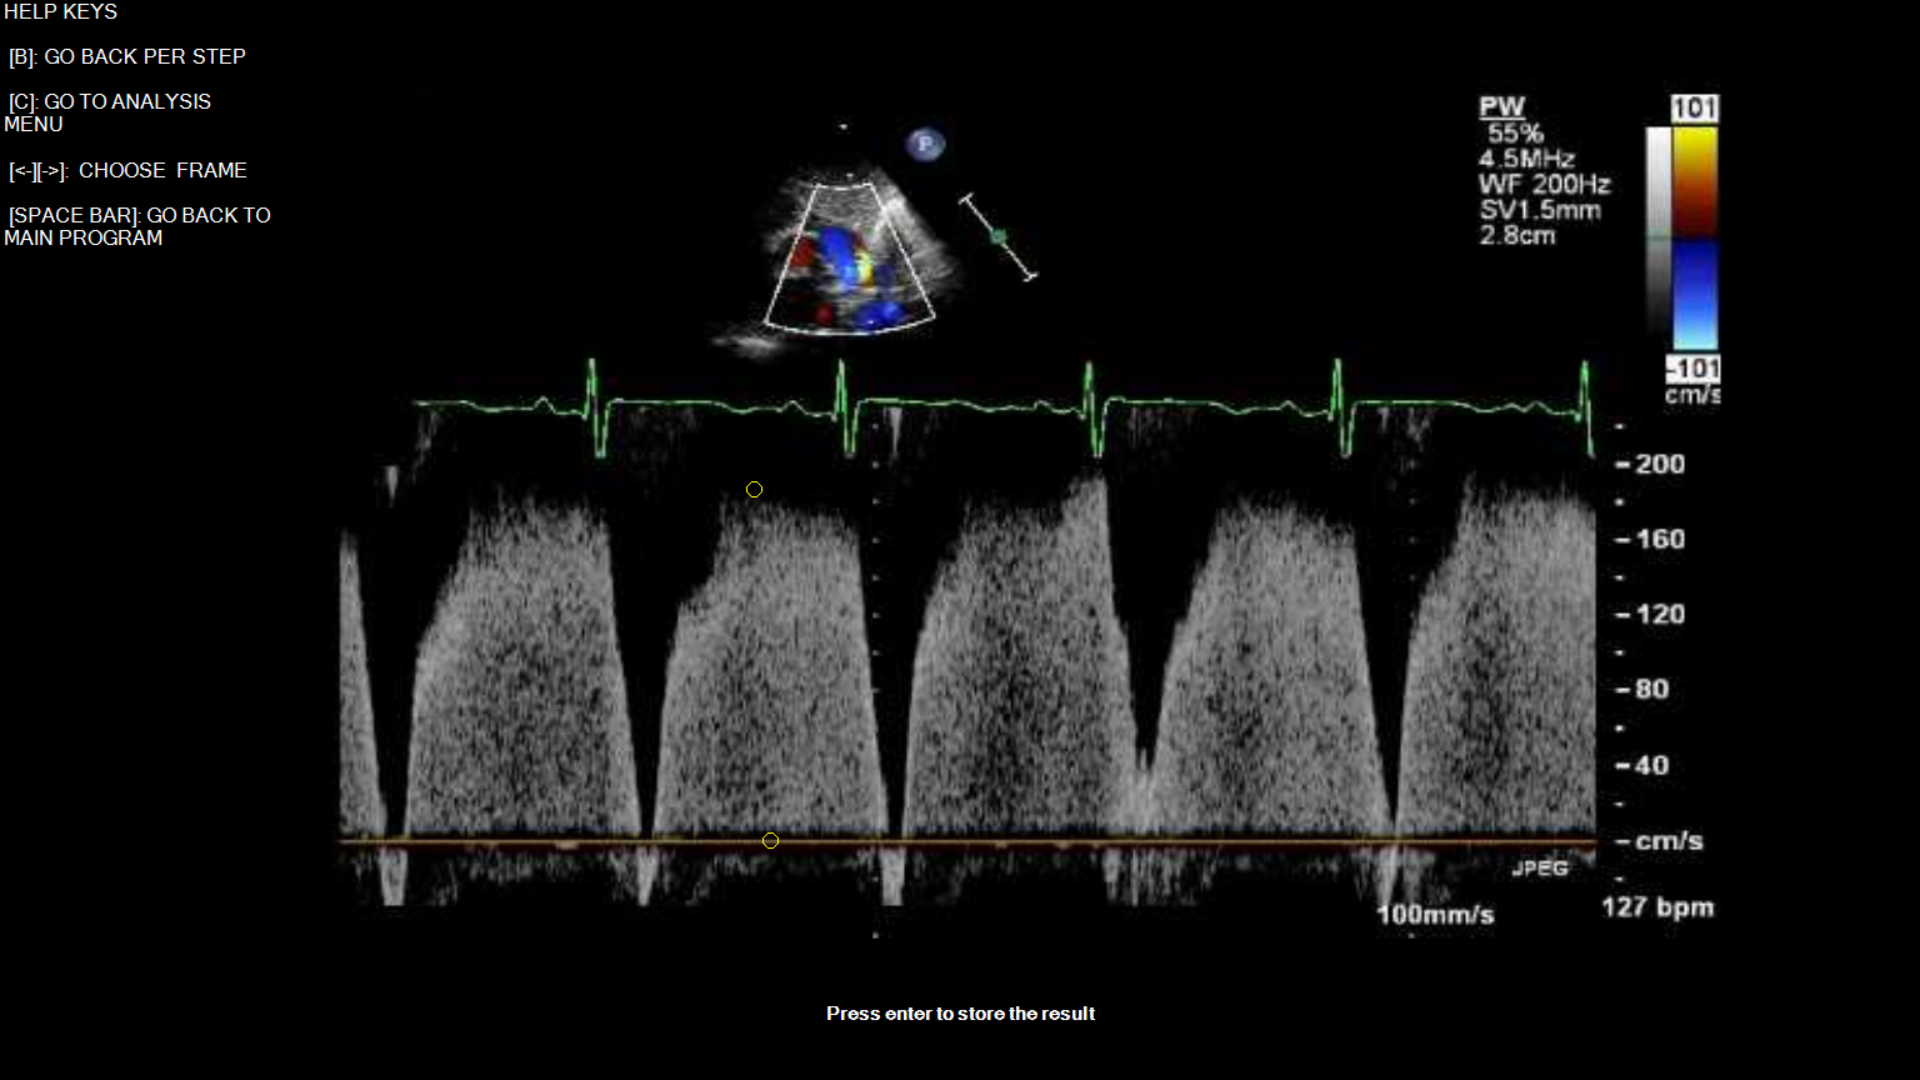

Demonstration of PDA Measurement